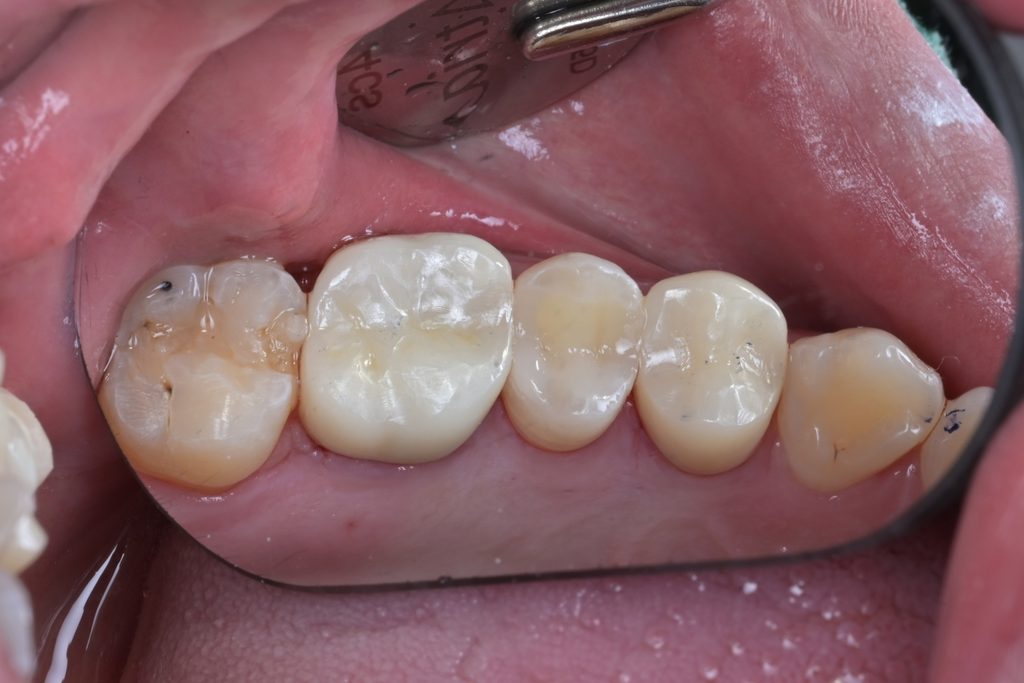

치료 후 최종 마무리 및 결과

레진빌드업 완료 후, 교합지를 이용하여 반대편 치아와의 교합 접촉을 세밀하게 조정하고, 다이아몬드 버와 폴리싱 시스템을 사용하여 최종 연마를 진행했습니다.

[사진14: 협측면에서 본 최종 치